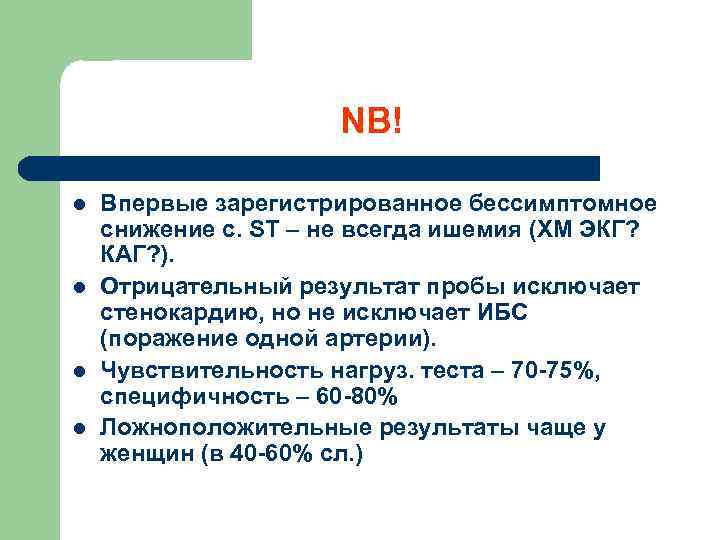

NB! l l Впервые зарегистрированное бессимптомное снижение с. ST – не всегда ишемия (ХМ ЭКГ? КАГ? ). Отрицательный результат пробы исключает стенокардию, но не исключает ИБС (поражение одной артерии). Чувствительность нагруз. теста – 70 -75%, специфичность – 60 -80% Ложноположительные результаты чаще у женщин (в 40 -60% сл. )